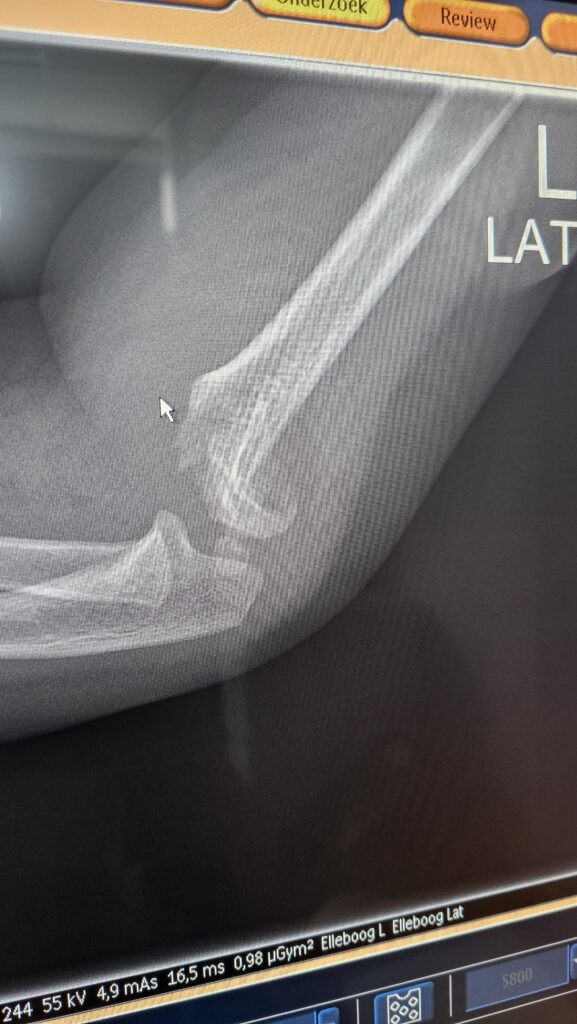

20:00 Pechvogel

Een vader belt voor zijn zoontje van 2,5 jaar. Hij viel van de picknicktafel en blijft maar huilen. Ik zie hem op de praktijk en maak röntgenfoto’s. Daar is een bovenarmsbreuk (supracondylaire humerusfractuur)

zichtbaar met dislocatie. De traumachirurg in Leeuwarden stelt dat het een operatie-indicatie is. Hij vraagt “Is de arm neurovasculair intact?”. Hm, hoe beoordeel je dat adequaat bij een peuter? In overleg besluiten we dat het toch de ochtendboot kan worden die om 06.50 uur vertrekt richting de wal. De andere huisarts helpt mij om gips aan te leggen voor de tussentijd. De dag erna krijg ik een Siilo-bericht van de traumachirurg: K-draden succesvol geplaatst en vanavond komen ze terug naar het eiland met de laatste boot.